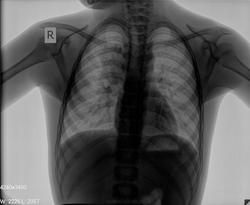

Мальчик 2000 г.р., направлен педиатром с диагнозом: Пневмония?

снимки

ogk.jpgogk_2.jpg